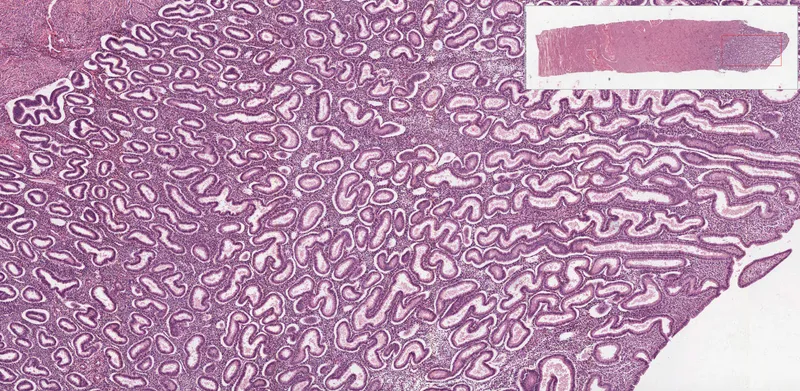

- Proliferative Phase (Follicular): Estrogen-driven (E₂).

- Endometrial glands & stroma proliferate; glands are straight, tubular.

- Secretory Phase (Luteal): Progesterone-driven (P₄) post-ovulation.

- Glands become tortuous ("saw-tooth"), coiled; subnuclear glycogen vacuoles appear, then luminal secretions. Spiral arteries lengthen & coil. Stromal edema, predecidual changes.